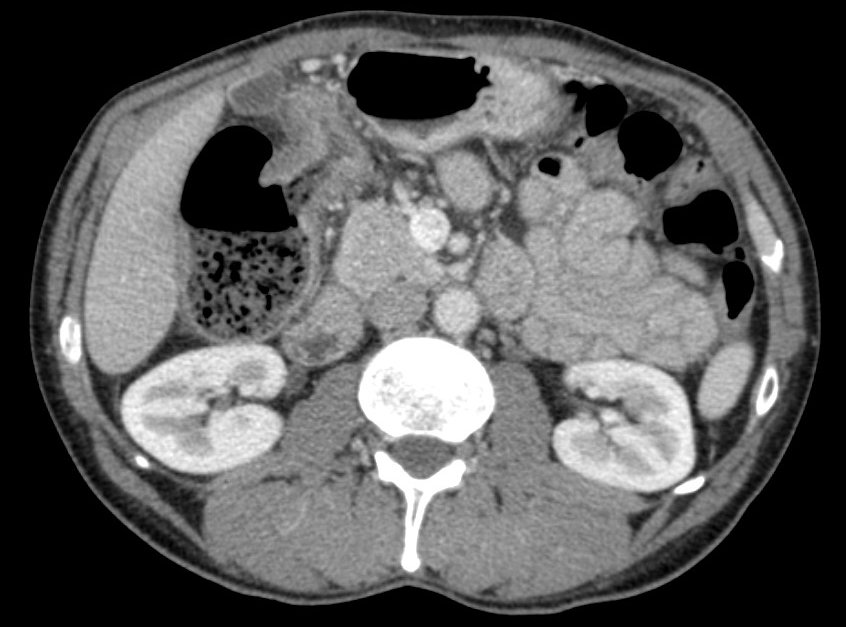

- Pancreas